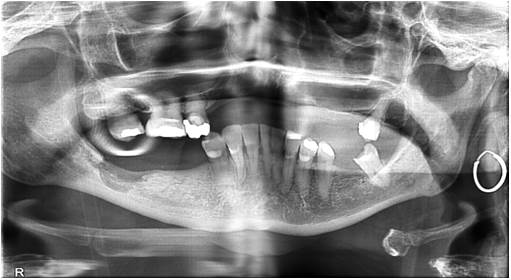

🤍 Cómo diagnosticamos en clínica

🔍 Nuestro protocolo combina:

1. Historia clínica + exploración detallada.

2. CBCT (TAC 3D): valora densidad y arquitectura ósea.

3. Correlación biológica: estudios recientes han demostrado sobreexpresión de mediadores inflamatorios en tejidos FDOJ.

¿Por qué no aparece en radiografías normales?

Porque muchas veces la alteración está en la médula ósea, y solo se detecta con CBCT o ecografía transalveolar.